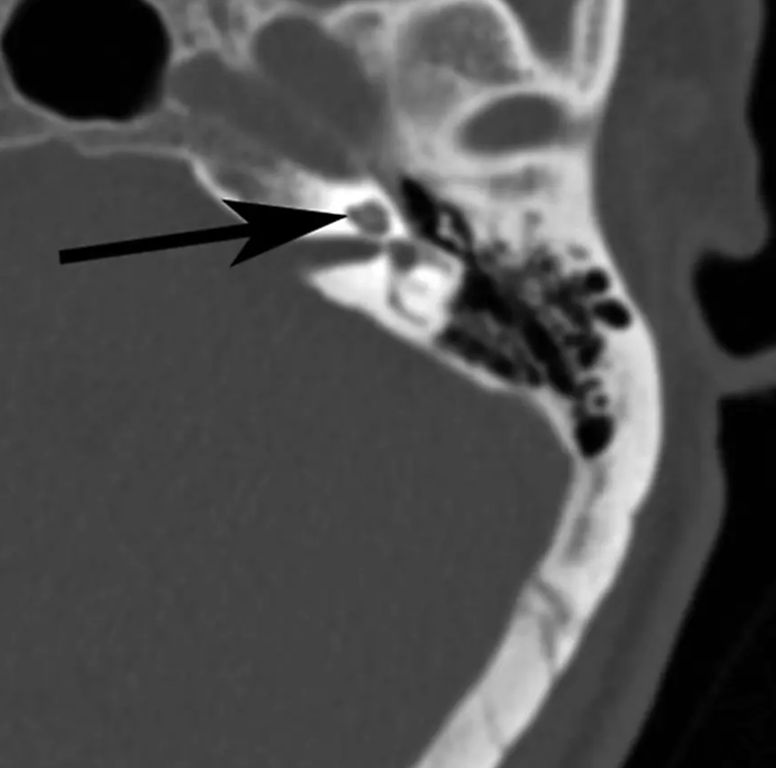

Cochlea

notion image

Vestibule

• lateral and posterior to cochlea

Malleus

• lateral and anterior to cochlea

Superior semicircular canal

• oriented in vertical plane perpindicular to long-axis of petrous temporal bone